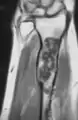

X-ray showing enchondromas localized in the lower part of the radius of a 37-year-old patient affected with Ollier disease

MRI showing enchondromas localized in the lower part of the radius of a 37-year-old patient affected with Ollier disease